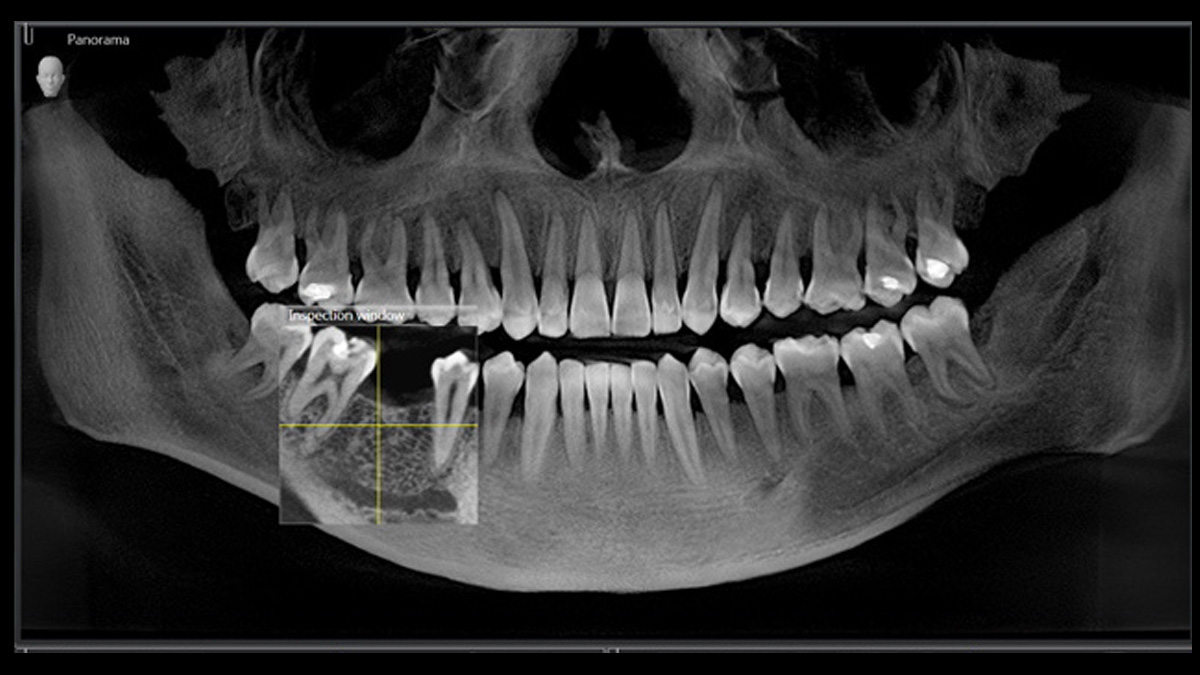

Digitale Röntgen

Das hochwertige 2D- / 3D-Röntgengerät mit umfassendem Leistungsspektrum für jede Praxis. Ob als reines 2D-Gerät oder inklusive 3D-Modul – der Orthophos S ist ein zuverlässiger Partner und optimiert für die täglichen Aufgaben in der Praxis. Sein CsI-Plus-Sensor mit Autofokus-Funktion sorgt für zeichenscharfe Aufnahmen auch in anatomisch schwierigen Fällen und der patentierte Okklusalaufbiss positioniert Patienten automatisch. Für den Einsatz in der Kieferorthopädie ist das Gerät optional mit einem Fernröntgenausleger verfügbar. Und weil Zukunftssicherheit bei Dentsply Sirona großgeschrieben wird, sind Fernröntgenausleger und 3D-Modul auch jederzeit nachrüstbar.